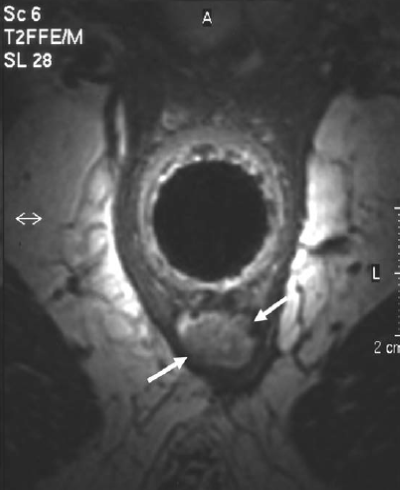

- MRI is the investigation of choice for anorectal abscess.

MRI scan is especially useful when there are no external signs of, but a high index of suspicion of anorectal abscess. It is also indicated in a complex fistulous abscess.